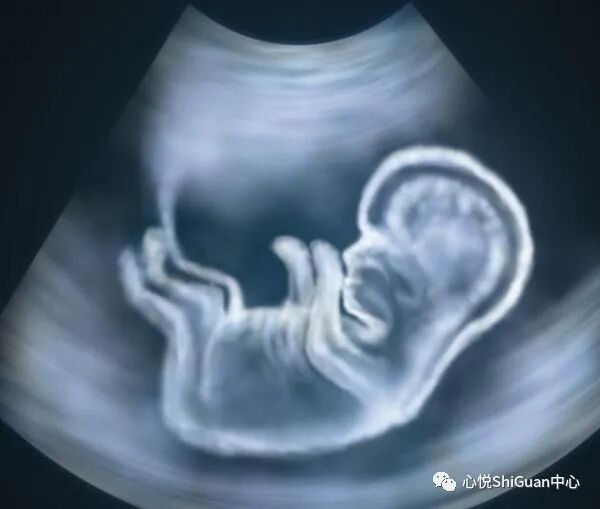

生儿育女是家庭幸福的延续,但是很多具有染色体异常或者家族遗传病史的夫妻只能被迫选择不育,害怕遗传到宝宝。现在,随着试管诊断和筛查技术的进步,第三代试管婴儿技术的研发就是针对于染色体异常人群,通过筛查移植前的胚胎选出更健康优质的胚胎来移植。

有遗传病担忧的备孕夫妻,特别是高龄备孕的夫妻,在备孕前做一个夫妻染色体检查流程的很有必要的。那么,广州第三代试管婴儿具体可以排除筛查哪些遗传病呢?